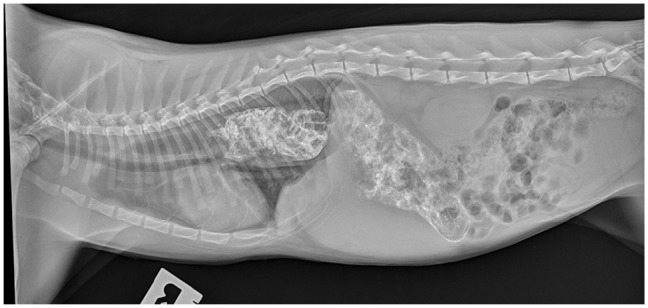

Case summary: A 6-month-old male entire domestic shorthair cat presented for presumptive Toxoplasma myopathy that was non-responsive to antiprotozoal therapy. Clinical features included marked macroglossia, dysphagia, regurgitation, truncal muscle hypertrophy, pelvic limb gait abnormalities and megaoesophagus. Relevant diagnostics included serial creatine kinase activity, cardiac troponin I, fluoroscopic swallow study and routine muscle histopathology. Ultimately, post-mortem histopathology with immunostaining demonstrated markedly decreased or absent staining for the rod and carboxy terminus of dystrophin, confirming a dystrophin-deficient muscular dystrophy (MD). The misdiagnosis of toxoplasmosis was based on an increased IgG titre and muscle histopathology submitted to a local laboratory. Treatment for megaoesophagus included vertical feeding of wet food only, sildenafil and omeprazole. Dysphagia and regurgitation improved moderately. Presumptive hyperaesthesia and muscle pain were managed with anti-inflammatory doses of prednisolone. The patient was ultimately euthanased as a result of progressive MD signs and uraemia at 2 years of age.

Relevance and novel information: This case report highlights the collective clinical features of MD, as they could be considered pathognomonic for this rare condition and must be differentiated from other myopathies via specific immunostaining of muscle biopsies. This is crucial to obtain a correct and early diagnosis, allowing instigation of potentially valuable treatments. Megaoesophagus is an inconsistent feature in feline MD in addition to the more commonly observed oropharyngeal dysphagia. Management with a canned diet, sildenafil, omeprazole and upright feeding was beneficial with moderate improvement in the frequency of regurgitation. Prednisolone was thought to minimise the presumptive myalgia.